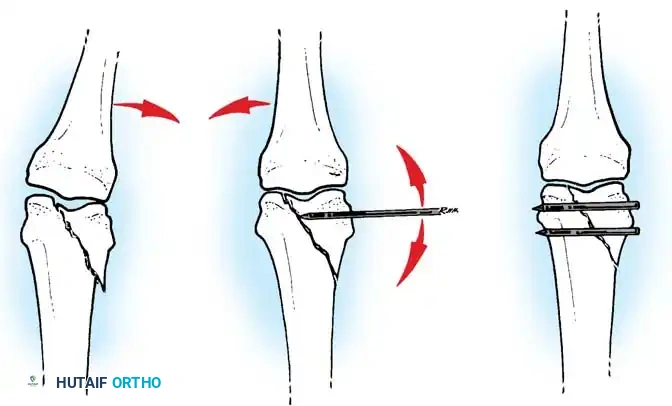

Fig. 64-68 A, Displaced, unstable condylar fracture usually requires open reduction and fixation. B, Manipulation of fracture using intact collateral ligament may permit insertion of Kirschner wire to hold reduction. C, Two wires may be necessary to avoid rotation of reduced fragment.

Fig. 64-67 A and B, Condylar fracture fixed with Kirschner wires.